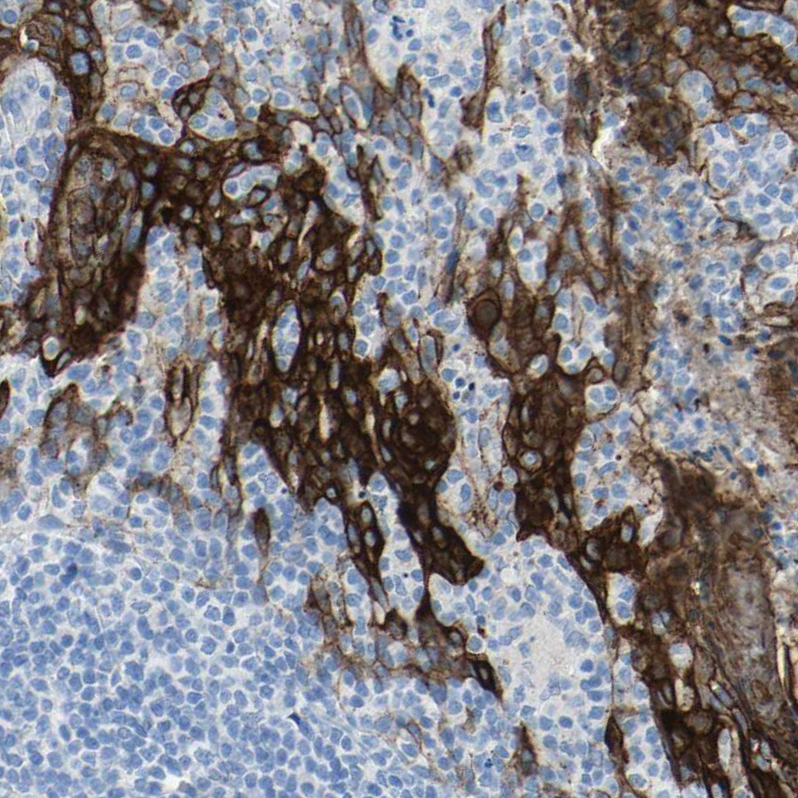

Immunohistochemistry analysis in human esophagus and cerebral cortex tissues using HPA011911 antibody. Corresponding DSC2 RNA-seq data are presented for the same tissues.